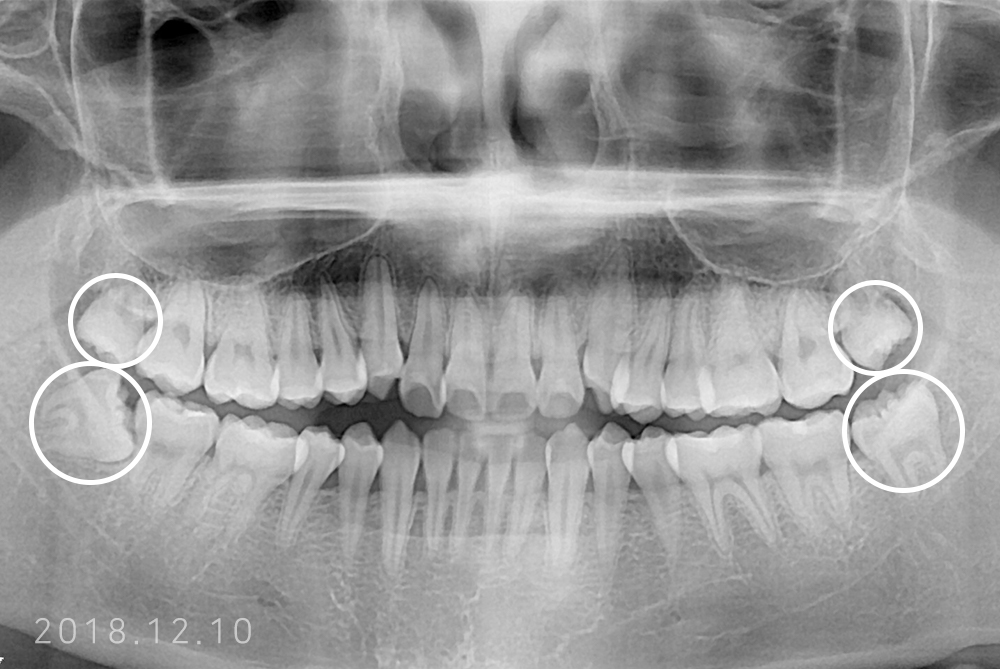

[사랑니] 매복 사랑니 발치

치료전 : 2018-12-10